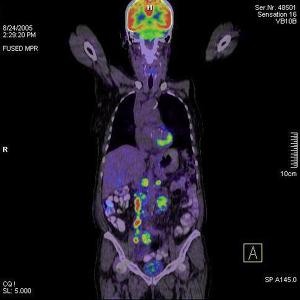

A PET/CT (pozitronemissziós tomográf és egy CT kamera egy készülékben) vizsgálatok nem csak azok számára adnak választ, akik valamilyen rákos megbetegedéssel érkeznek hozzánk, hanem azok számára is, akik szeretnének meggyőződni arról, hogy szervezetükben nincs jelen semmilyen daganat.

A vizsgálat során a szervezetbe intravénásan egy FDG nevű anyagot adunk, (ez egy szőlőcukor molekulához kapcsolt fluor izotóp) amely azután szétterjed a szervezetben, hiszen a sejtek működésük során cukrot használnak fel. A vizsgálati képeken látható színes foltok jelölik azokat a gócpontokat, ahol ez az anyag felhalmozódik, ugyanis a daganatok sokkal több cukrot használnak fel működésük során, ezáltal a fluor is felhalmozódik és a PET kamera ezt érzékeli.

A CT képekre rávetített PET felvételek segítségével nagyon pontosan lokalizálható az elváltozás, valamint annak pontos mérete is meghatározható. A PET/CT akár már 2-3 mm-es állapotában felfedi a daganatos elváltozásokat, ami azért fontos, mert a korai stádiumban a rák nagyon jó eséllyel gyógyítható, ha időben megkezdik a megfelelő kezelést.